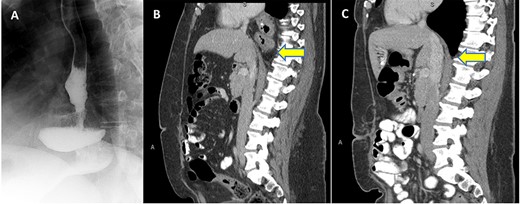

Patient is a 43-year-old female with past medical history of a SG and an ‘anterior’ hiatal hernia repair at an outside facility 11 years ago for a body mass index (BMI) of 74.3 Kg/m2 at index SG. The reported hiatal hernia repair at index SG involved approximation of the right and left crura with one stitch anterior to the esophagus without a formal standard posterior or mediastinum esophageal dissection. She presented to our clinic with 3 years history of progressive dysphagia and heartburn. Preoperative upper gastrointestinal (UGI) series and computed tomography (CT) scan demonstrated the migration of almost all of the sleeved stomach into the thoracic cavity with a partial organoaxial volvulus (Fig. 1 A and B). UGI endoscopy showed 10 cm hiatal hernia with intrathoracic migration of the SG with esophagitis grade B (Los Angeles classification).

(A) UGI series with SLG in an intrathoracic position; (B) Preoperative CT scan in sagittal view with evidence thoracic migration of the stomach with partial organoaxial volvulus; (C) CT scan 1 year postoperatively confirming intact repair.

The recovery was uneventful and the patient was discharged home on postoperative day 3. The patient was symptoms free upon 2 years follow-up with BMI of 33. CT scan 1 year postoperatively was performed for symptoms not related to surgery confirmed an intact repair (Fig. 1C).